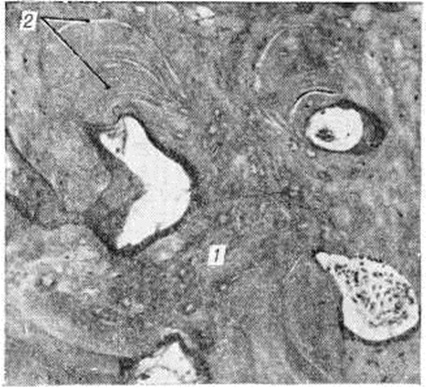

При микроскопическом исследовании обнаруживается, что патологический избыточное костеобразование идёт во всех костях скелета как в области эпифизарного хряща (ростковой зоны), так и по ходу диафиза. Очень редко наблюдается периостальное костеобразование. В костномозговых пространствах в некоторых случаях обнаруживают толстые слоистые структуры, располагающиеся вокруг капилляров и представляющие собой патологический остеоны. В других случаях костномозговые пространства бывают выполнены пластинчатой костной тканью с многочисленными дугообразными линиями склеивания. Встречаются балки из незрелой грубоволокнистой костной ткани. В пластинчатой кости уменьшено количество остеобластов, распределение их в костной ткани неравномерное. Явлений резорбции кости почти не наблюдается. Костномозговые пространства резко сужены, выполнены фиброретикулярной тканью. Лишь местами можно встретить участки костного мозга. В зоне энхондрального окостенения основная субстанция хряща не подвергается резорбции, как это имеет место в физиологический условиях, а даёт образование костной ткани, сначала в виде округлых островков (рисунок 1), а затем широких костных перекладин, по краям которых видны остатки основной субстанции хряща. По мере удаления от эпифизарного хряща вещество кости приобретает пластинчатое строение (рисунок 2).